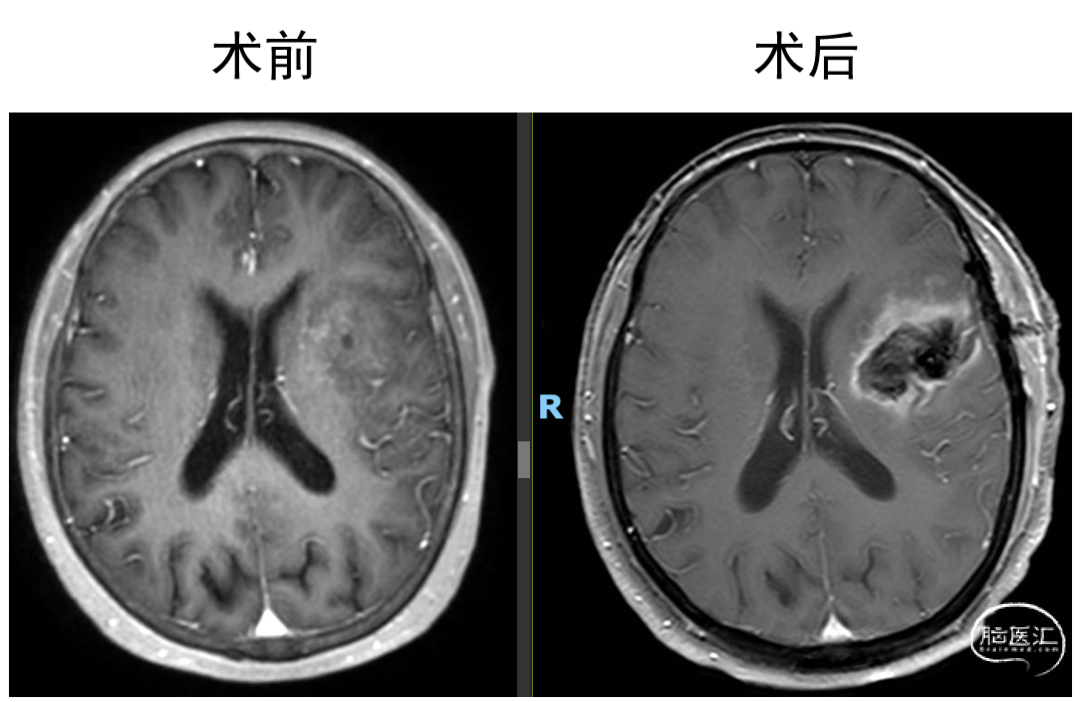

术后MR